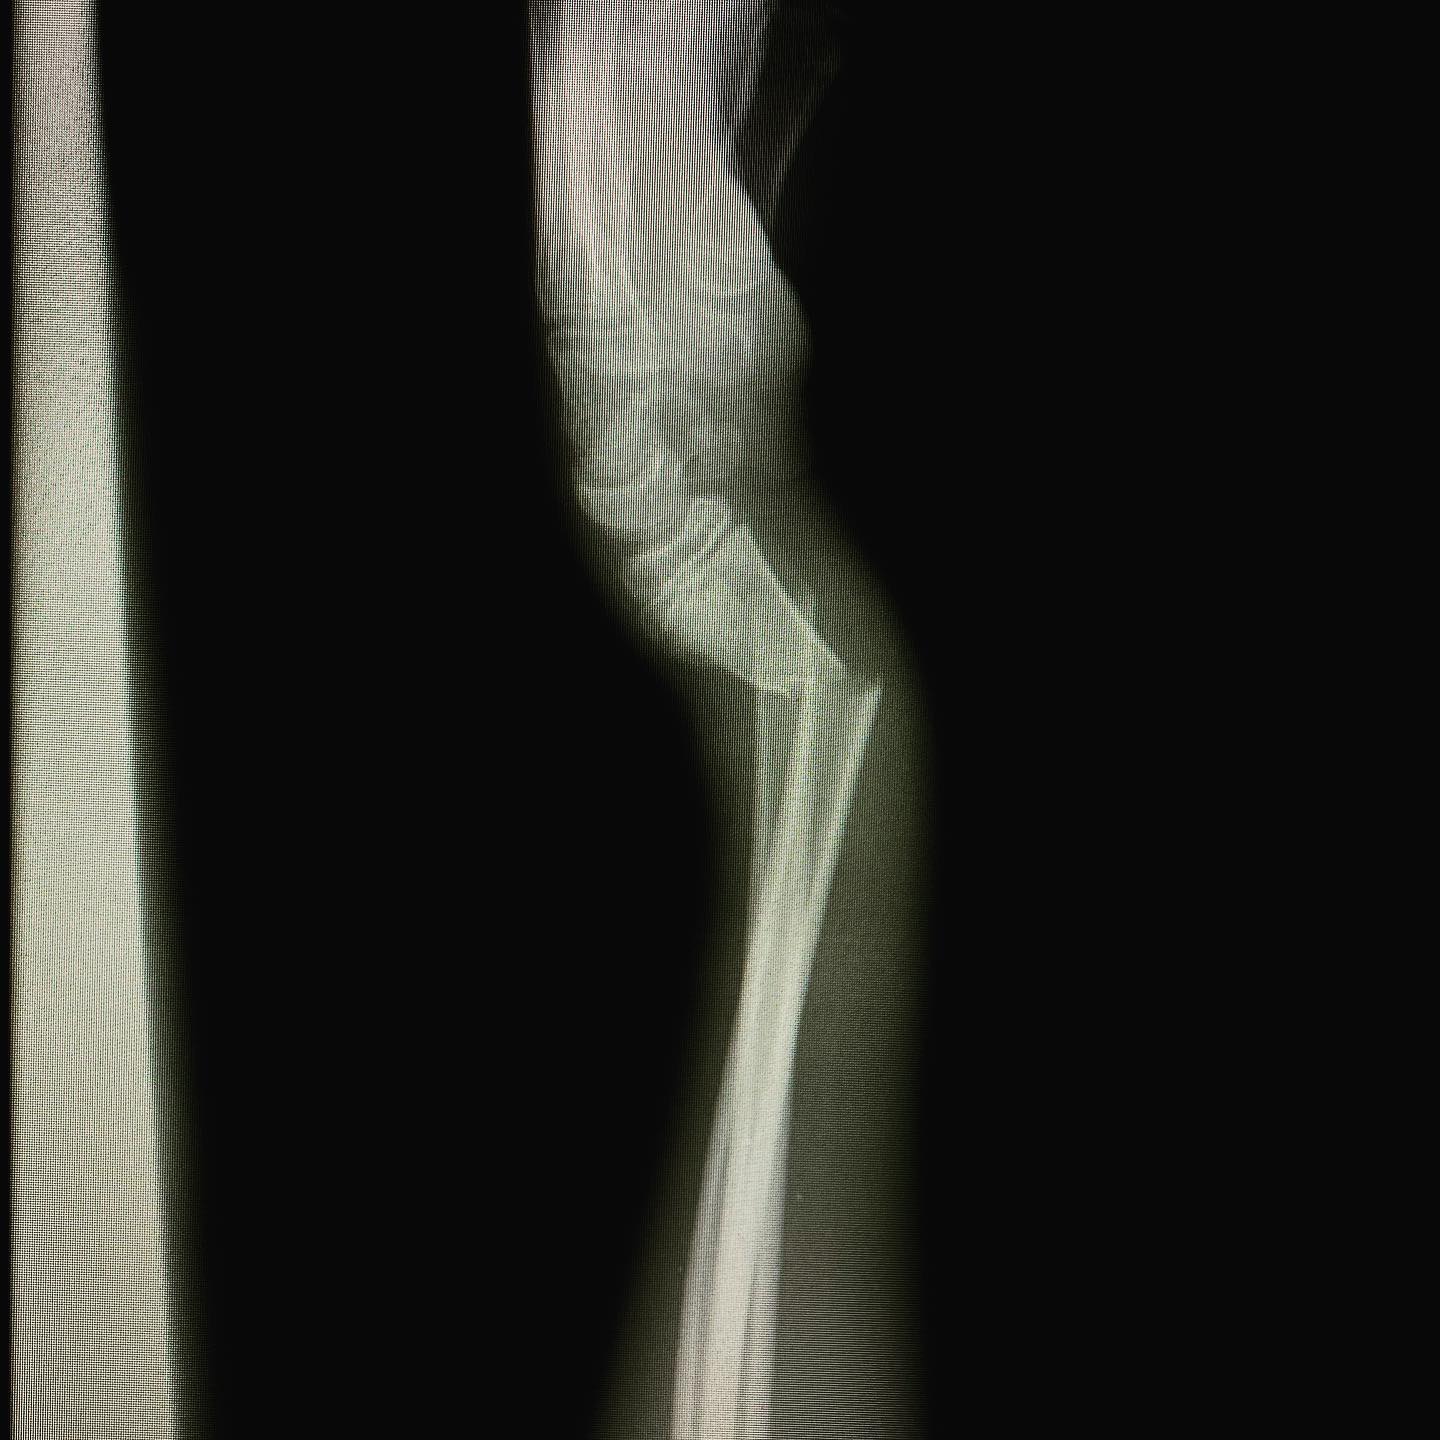

fractura de antebrazo

Cité a Josué para seguimiento y como ya está recuperado al 💯 de la cirugía por fractura de su antebrazo, le di el alta. En su visita me regaló una deliciosa sandía.🍉